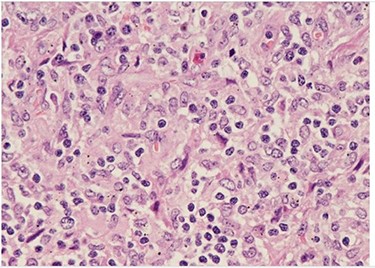

H&E (High power magnification, 40×) shows characteristic large activated lymphoid cells, karyorrhectic debris and histiocytes. The histiocytes are enlarged with crescentic nuclei and phagocytized nuclear debris. Neutrophils are absent.